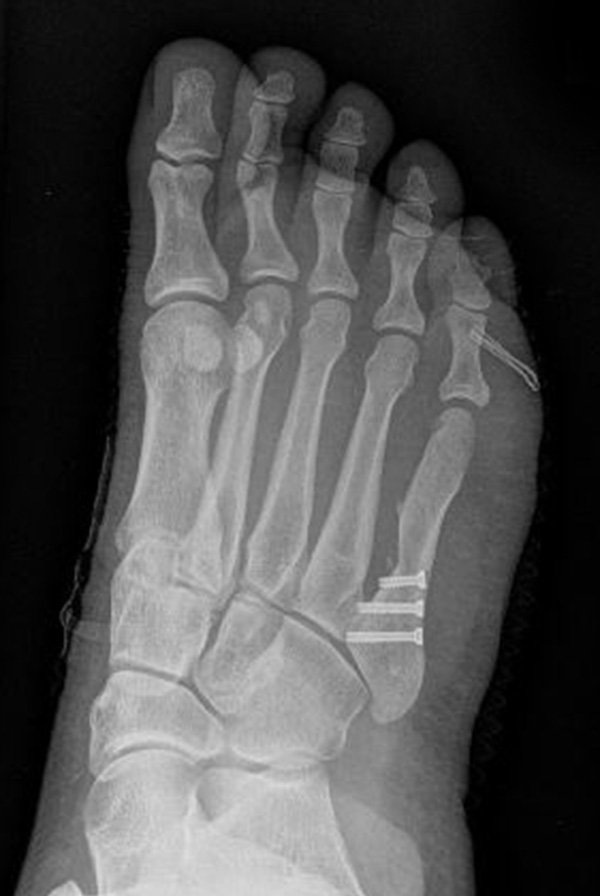

Abb. 7 a, b: Typ II Deformität mit prä- (a) und postoperativem Röntgenbild (b) mit K-Draht Osteosynthese und gleichzeitiger Hallux valgus Korrektur.

Abb. 8 a, b, c: Typ III Deformität mit prä- (a) und postoperativem Röntgenbild (b, c) mit Schrauben-Osteosynthese.